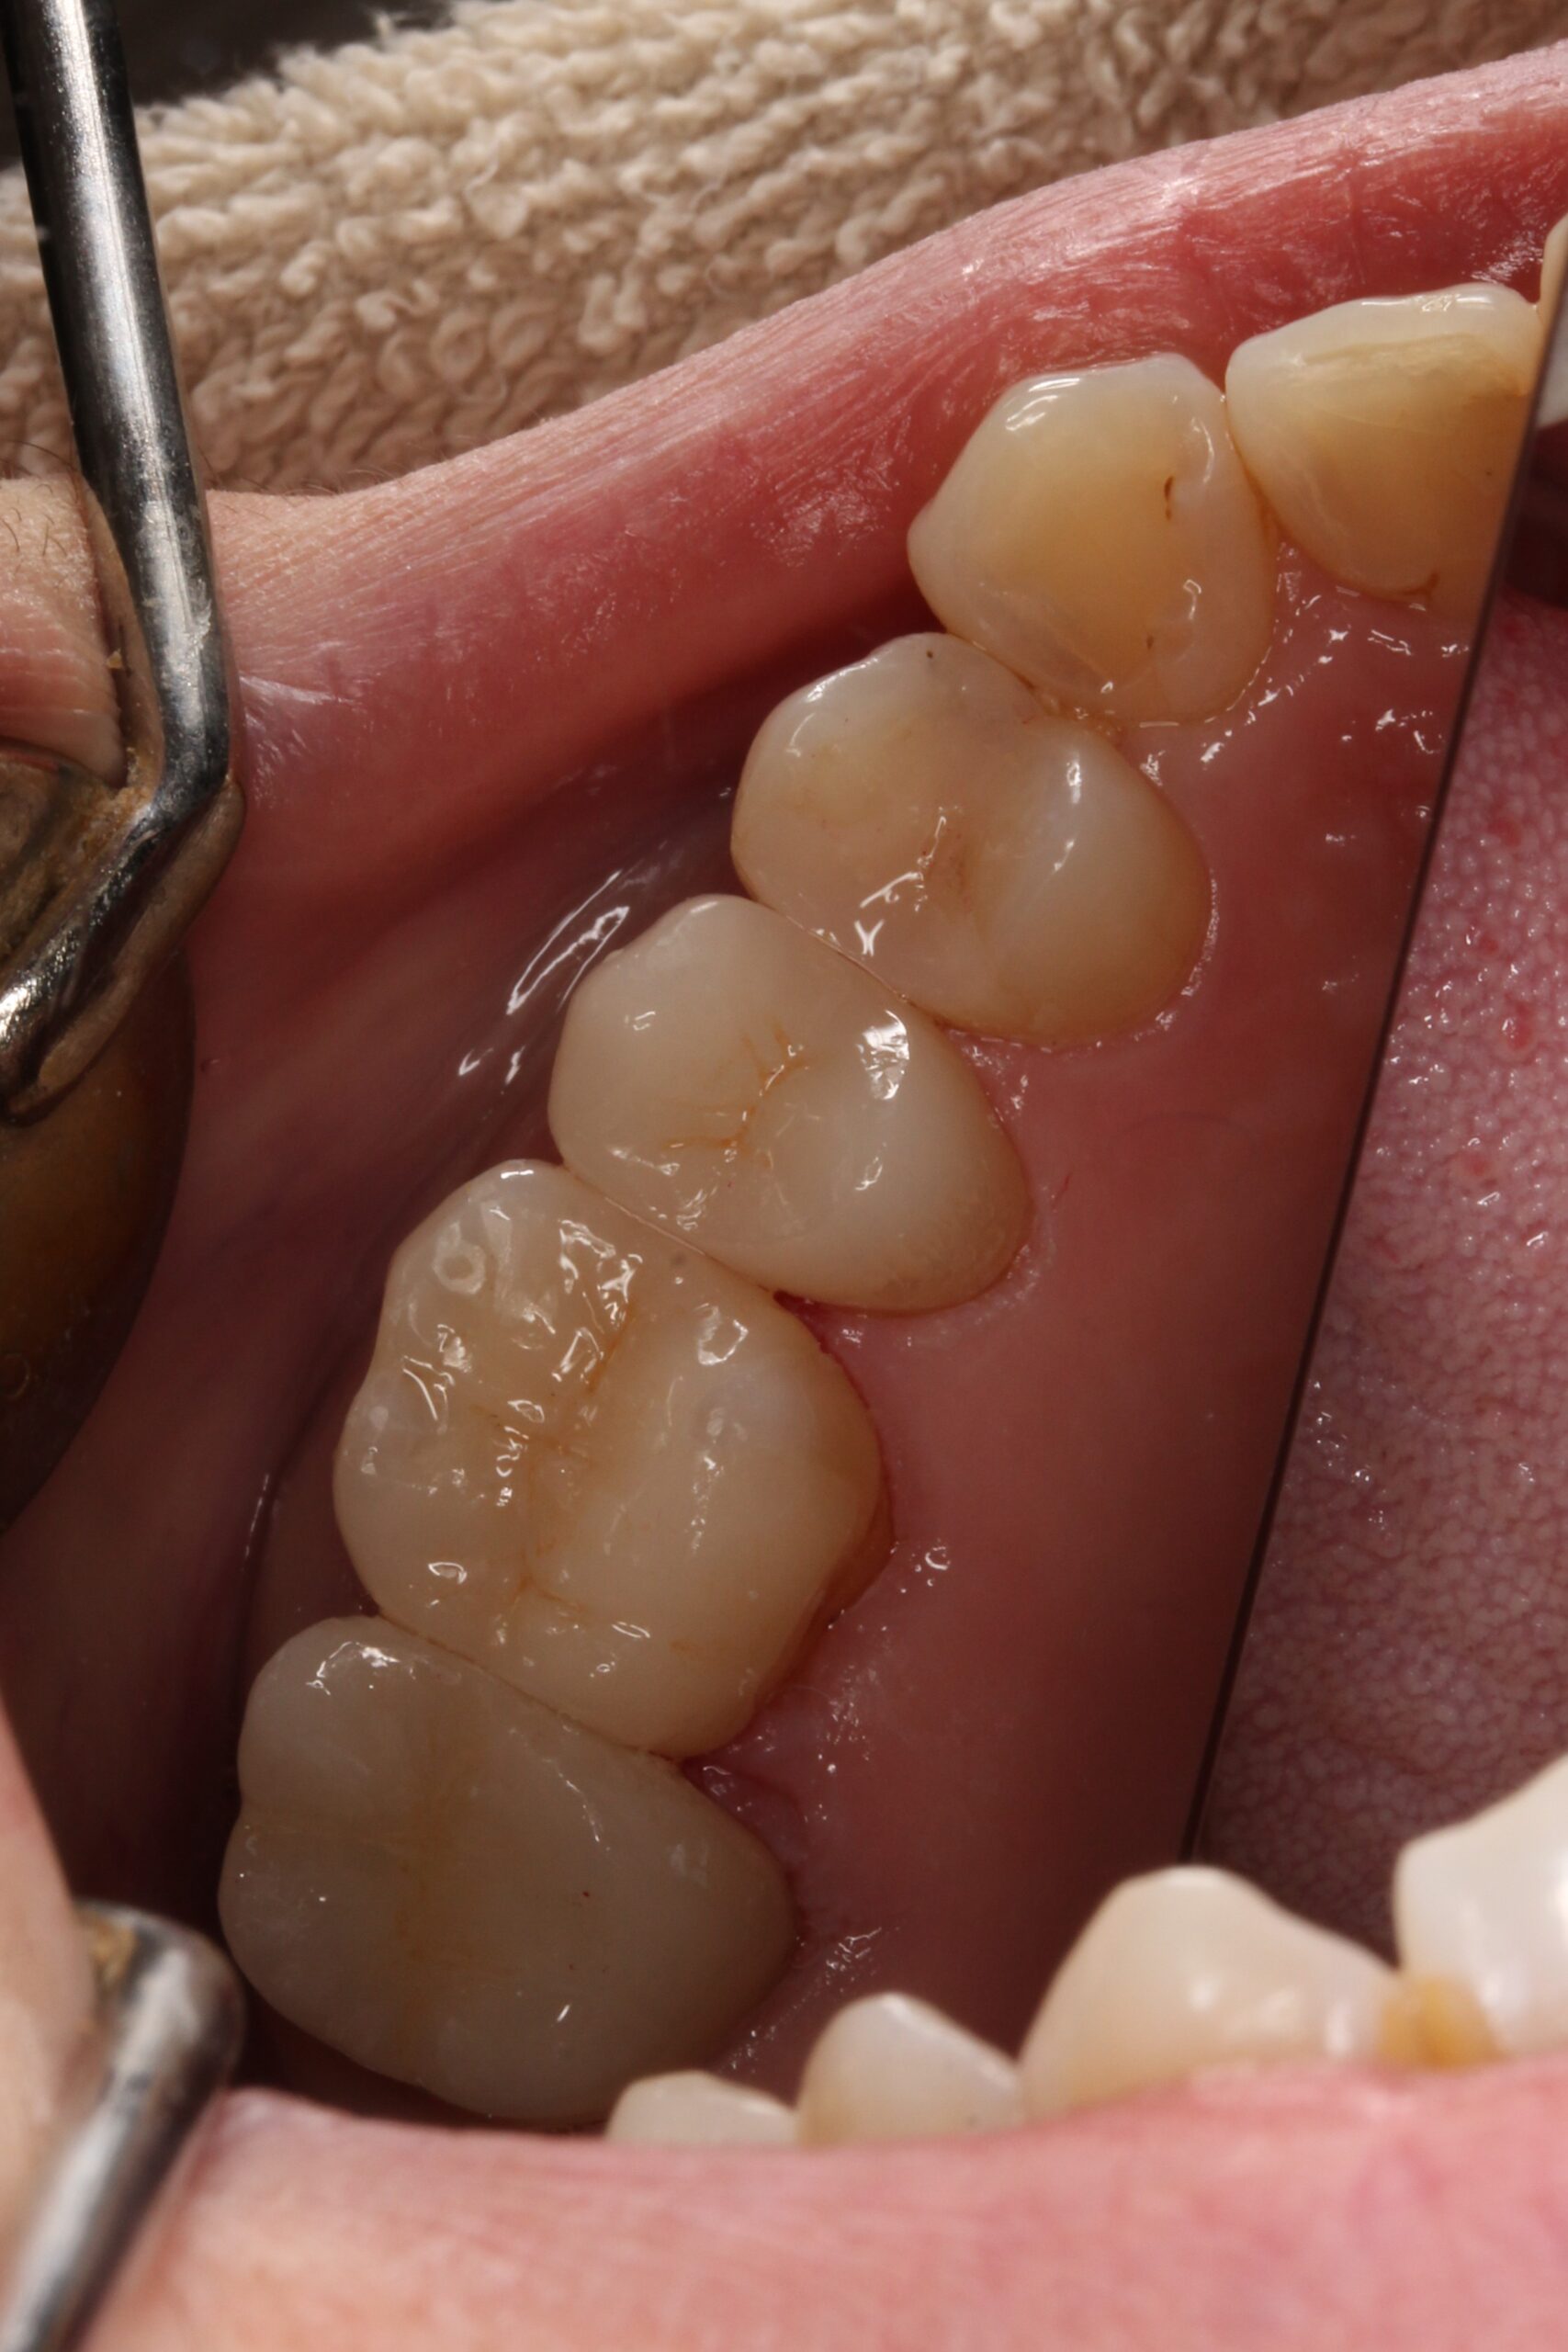

フロスが引っかかる浮いて合っていないジルコニアインレーをセラミックに交換

• Before

After